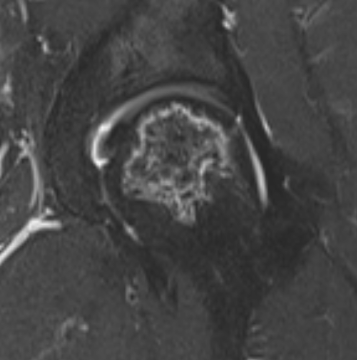

T2 Double Line Sign

Two lines virtually diagnostic of AVN

- outer line / low signa intensity

- inner line / high signal intensity / hypervascular granulation tissue